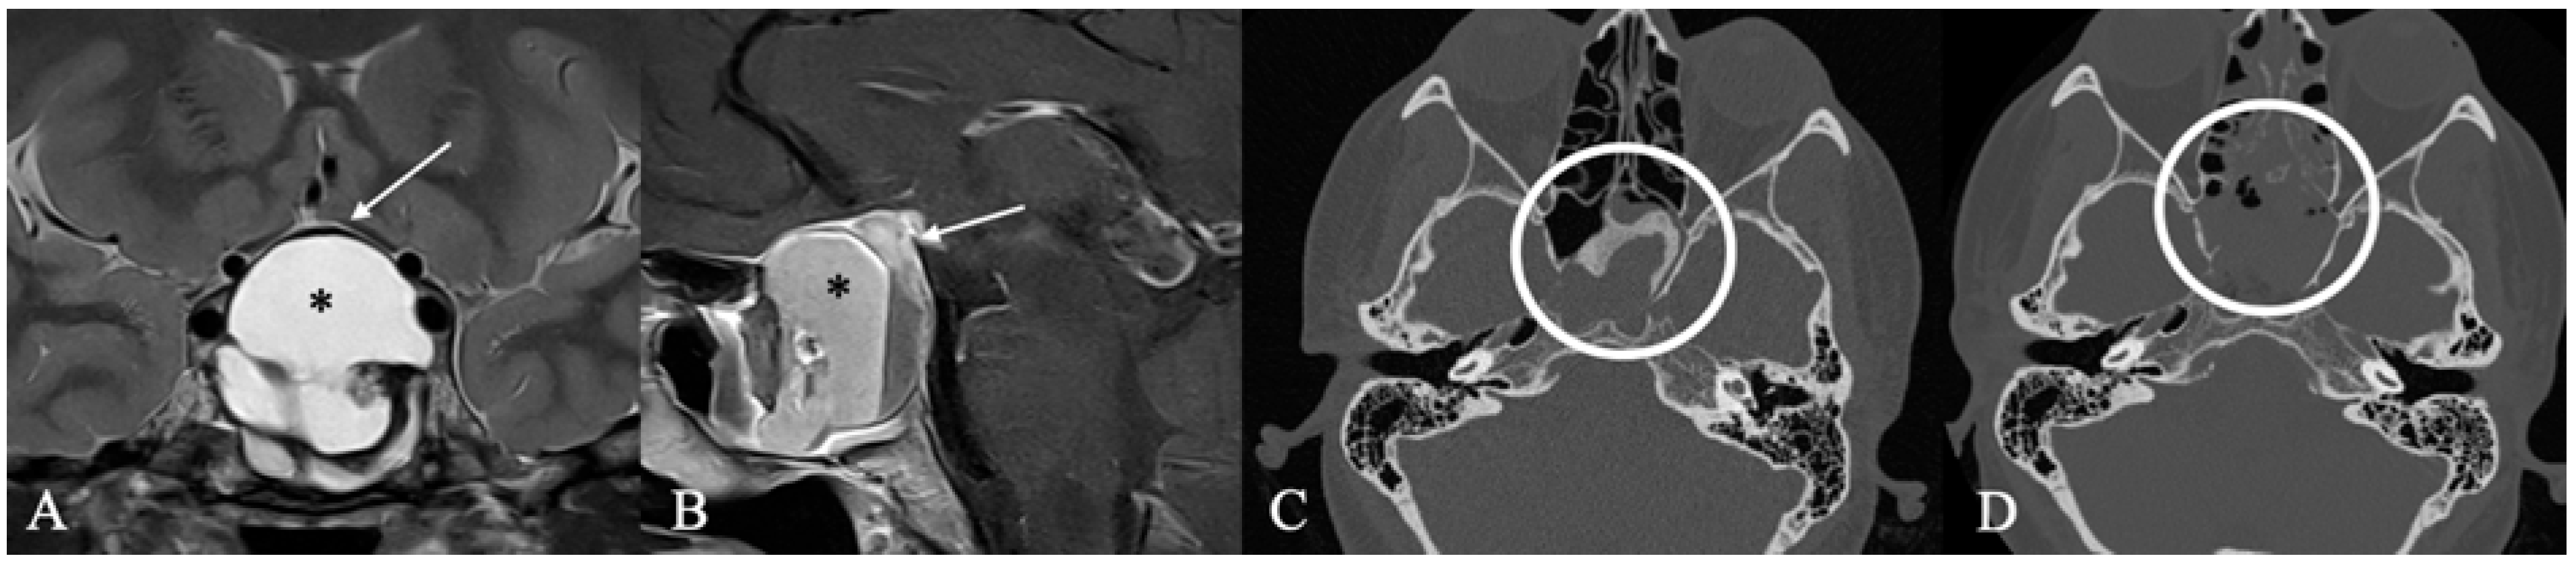

4.2. Differential Diagnoses and Case Presentations